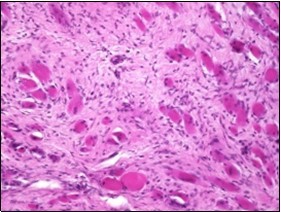

On microscopy, a collagen- rich, minimally cellular, fibrotic soft tissue nodule is exemplified which simulates a scar or conventional fibroma. The neoplasm is comprised of uniform, plump, fibroblastic or myo-fibroblastic cells encompassed in a collagen-rich stroma with infiltration and entrapment of skeletal myocytes 5, 6. Cogent histological examination depicts replacement of muscle fibres and muscle mass with fascicles of fibrous tissue comprised of mature fibroblastic cells, thereby conferring fibrosis 6. Figure 1, Figure 2, Figure 3, Figure 4, Figure 5, Figure 6, Figure 7, Figure 8.

Figure 1.Fibromatosis colli depicting bundles of fibroblasts and myo-fibroblasts intermixed with a collagenous stroma and entrapped myocytes 9.